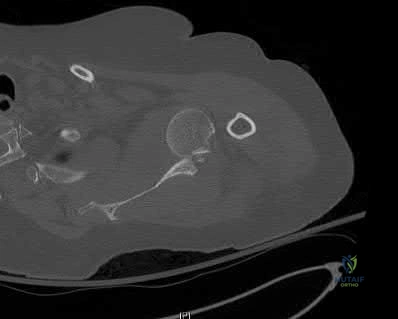

Question 19:

A 29-year-old male sustains an acetabular fracture in an MVC. Plain radiographs reveal a disruption of the iliopectineal line, a teardrop that is displaced medially, an intact ilioischial line, and an intact posterior wall. Based on the Judet-Letournel classification, which type of acetabular fracture is this?

Options:

- Posterior column

- Anterior column

- Transverse

- Both column

- T-shaped

Correct Answer: Posterior column

Explanation:

In radiographic evaluation of the acetabulum, the iliopectineal line represents the anterior column, and the ilioischial line represents the posterior column. Disruption of the iliopectineal line with an intact ilioischial line firmly indicates an isolated anterior column fracture. The radiographic teardrop is often displaced or disrupted in anterior column or anterior wall injuries.